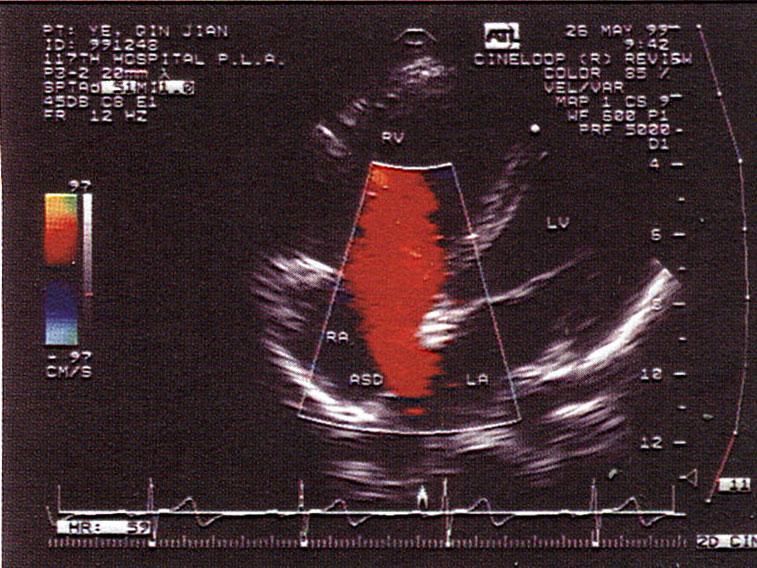

以上房间隔缺损属于哪型?(?)A.原发孔型B.继发孔型C.上腔型D.下腔型E.混合型

问题 以上房间隔缺损属于哪型?(?)

选项 A.原发孔型 B.继发孔型 C.上腔型 D.下腔型 E.混合型

答案 B